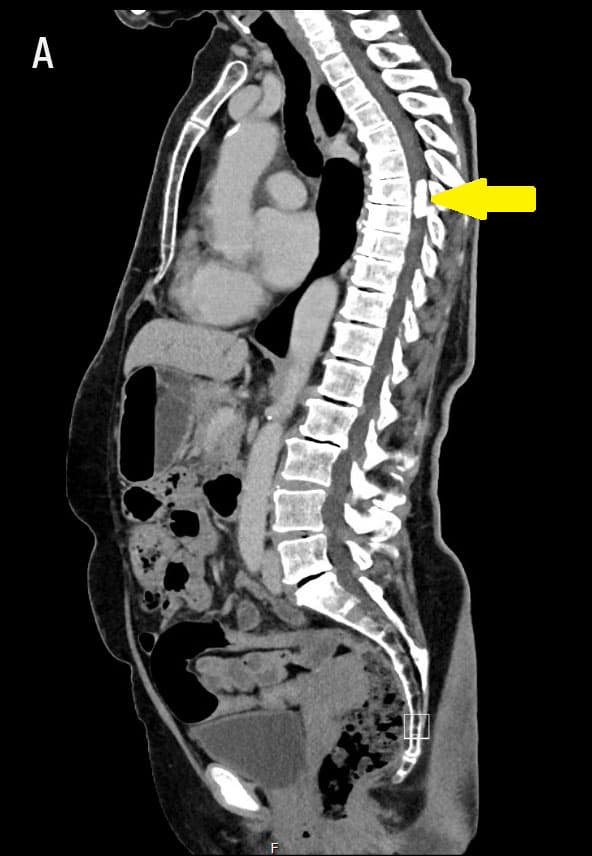

CT af thorax og abdomen blev oprindeligt foretaget som led i udredning for ovariecyster, men som bifund fandt man en 2,6 × 0,9 cm forkalket proces i spinalkanalen på niveau Th7-8 (A). En MR-skanning bekræftede en intradural, ekstramedullær proces med kompression af medulla spinalis.